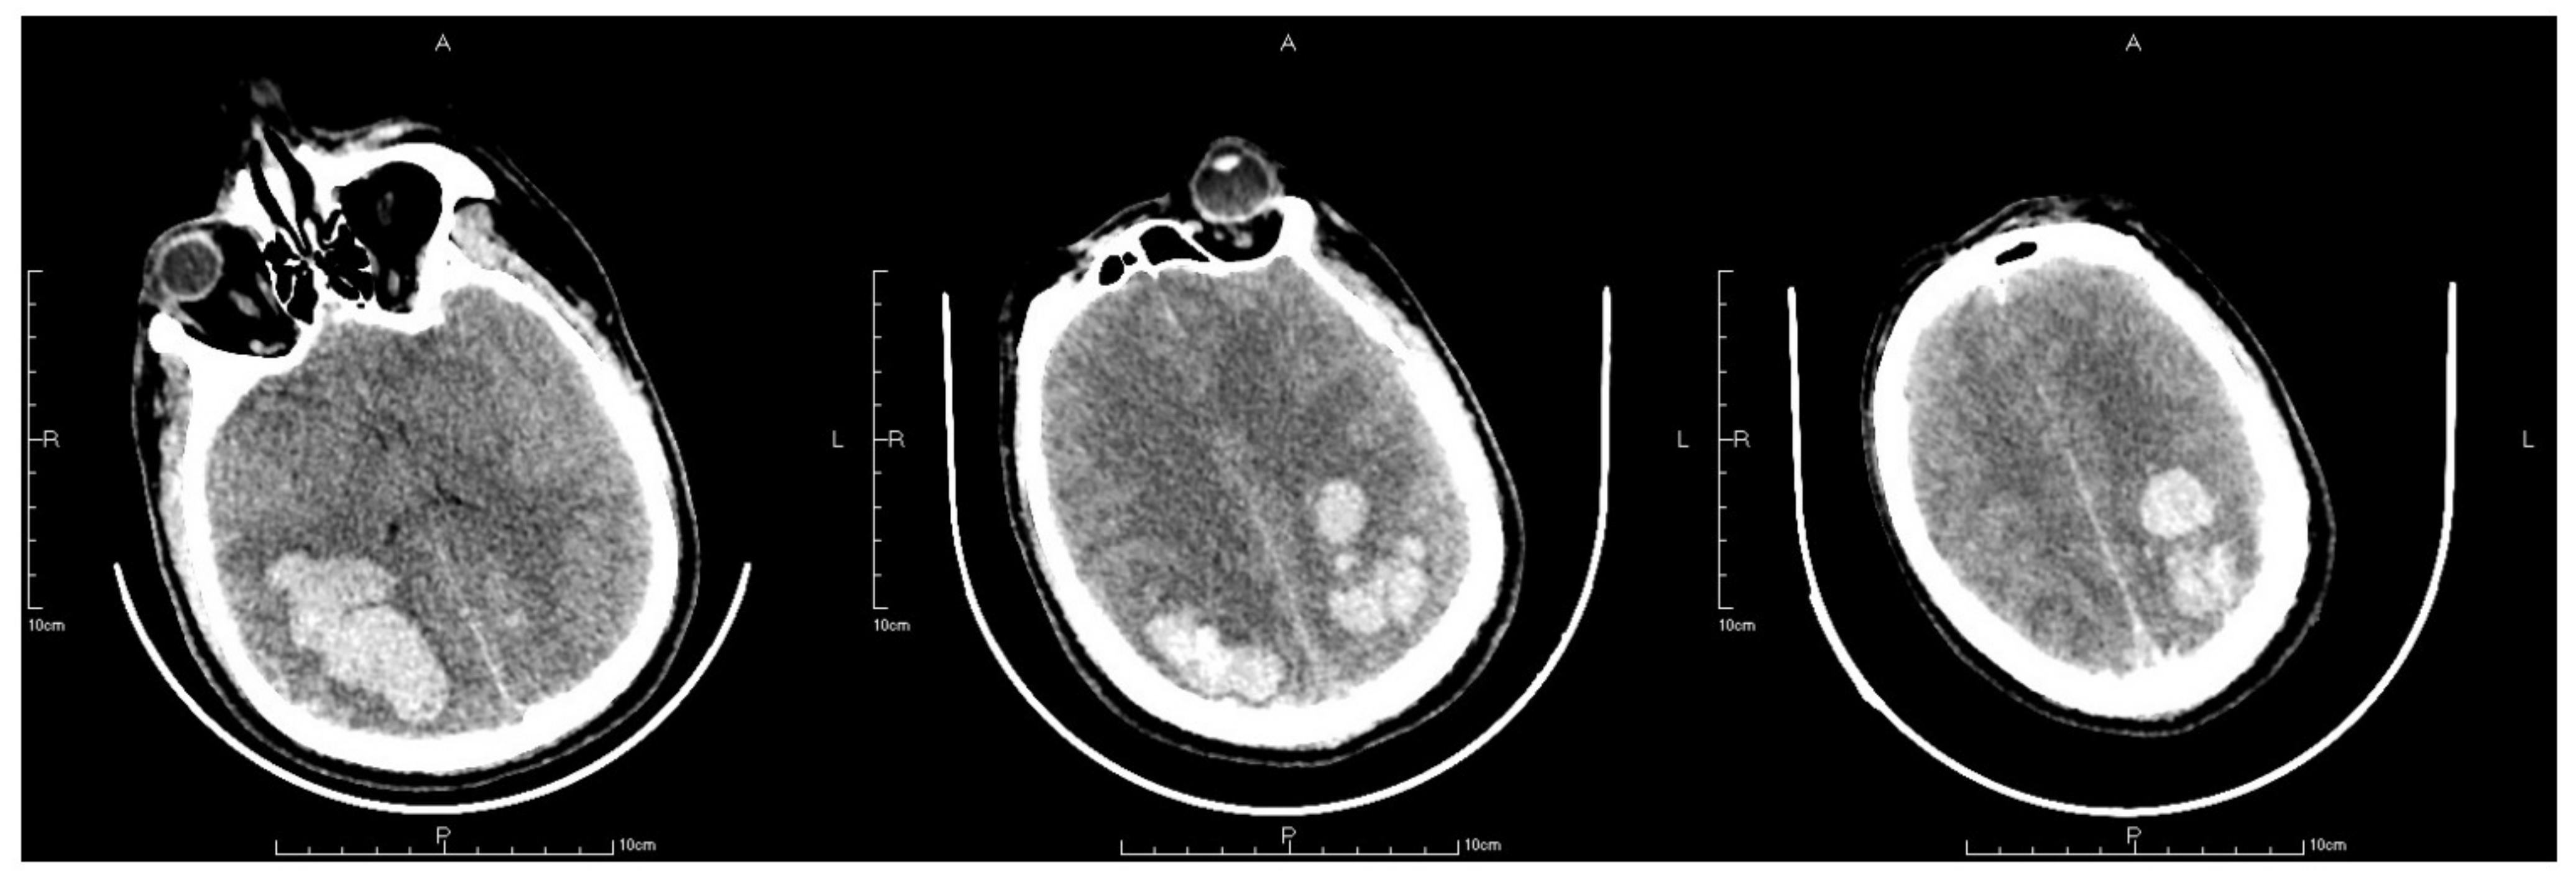

After the surgery, routine postoperative management was employed. Mask inhalation was applied constantly with a flow rate of 5 L/min; 250 mL mannitol was used to reduce the intracranial pressure; 8 mg noradrenaline was constantly pumped in to maintain blood pressure within a normal range; and 50 μg sufentanil was also pumped in for sedation and pain relief. However, 2 h after the surgery, the patient suddenly presented with vomiting and idiopathic myosis with a diameter of only 1.5 mm, and did not react to light. An emergency CT scan revealing a postoperative change after the thrombectomy was obtained. The CT scan showed expanded hemorrhagic areas along with bilateral intraparenchymal hematomas in the frontoparietal lobes (Figure 5). Concurrently, the emergency arterial blood gas revealed the following: pH, 7.296; PCO2, 32.6 mmHg; PO2, 63.5 mmHg; and cHCO3, 15.5 mmol/L. Emergency tracheal intubation with an invasive ventilator was implemented to ensure that the airway was unobstructed. Mannitol was applied again to enhance intracranial pressure reduction. Another cerebral CT scan was also obtained on the first postoperative day, which demonstrated that the hemorrhagic areas on the right frontoparietal lobes and epencephalon had further expanded (Figure 6). On the second postoperative day, the patient’s autonomous respiration and heartbeat ceased concomitantly with corectasis. The emergency electrocardiogram depicted an equipotential line, following which the patient was pronounced dead.

Figure 5.

The letter R, A, P, L in the figures refers to Right, Anterior, Posterior and Left, respectively. CT scan after thrombectomy showed postoperative changing with expanded hemorrhage areas in bilateral frontoparietal lobes together with bilateral intraparenchymal hematoma in the frontoparietal lobes.

Figure 6.

The letter R, A, P, L in the figures refers to Right, Anterior, Posterior and Left, respectively. Last CT before death showed hemorrhage areas on right frontoparietal lobes and further expansion of epencephalon.